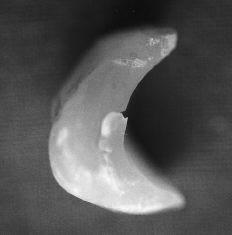

Figura 1. Artroplastia de silicona en semilunar.

Figura 2. Aspecto macroscópico del implante: desgaste y abrasión de la superficie.